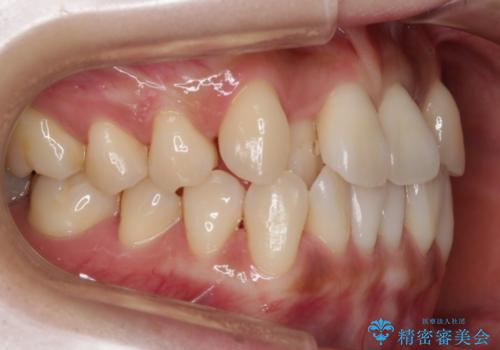

【非抜歯】左右の八重歯・前歯の反対咬合の改善 インビザライン

- 前歯のガタつきを主訴にご来院されました。

診査の結果、骨の厚みに余裕がなく幅の拡大とIPR(歯と歯の間を削り隙間を作る作業)のみでは歯周病に対する不安が残ることが懸念されたため、マイクロインプラントを用いて奥歯から順にすべての歯を後方移動させる方法によってスペースを作ることとなりました。